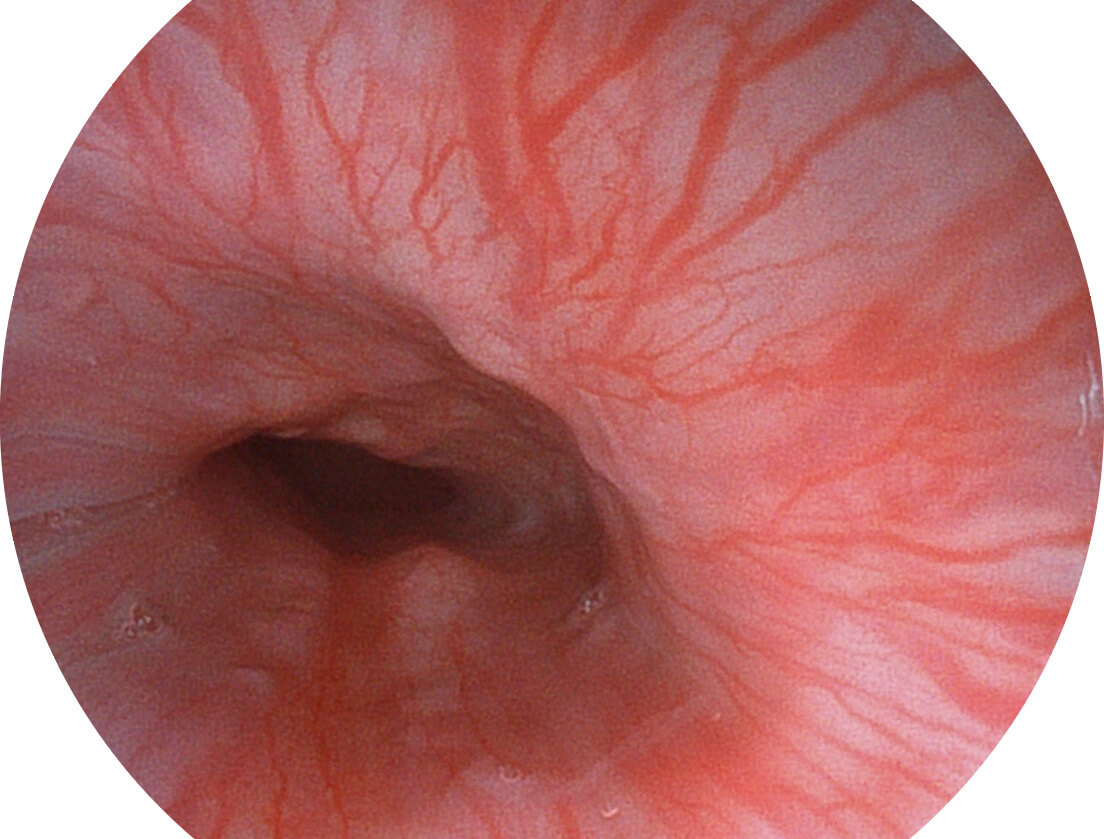

• 白光图像 SFI图像

• 白光图像 VIST图像